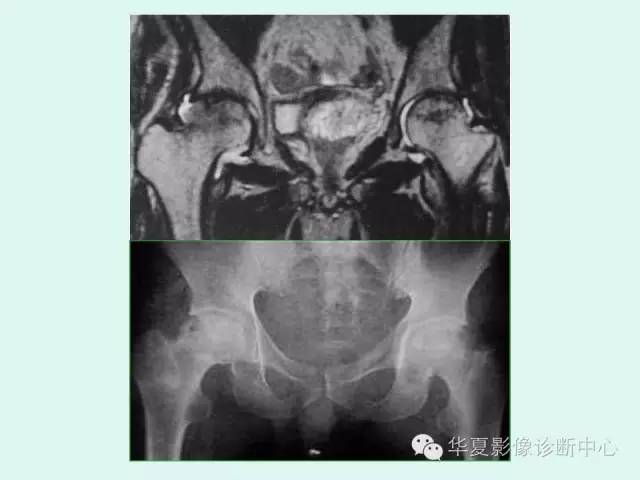

【PPT】股骨头缺血性坏死